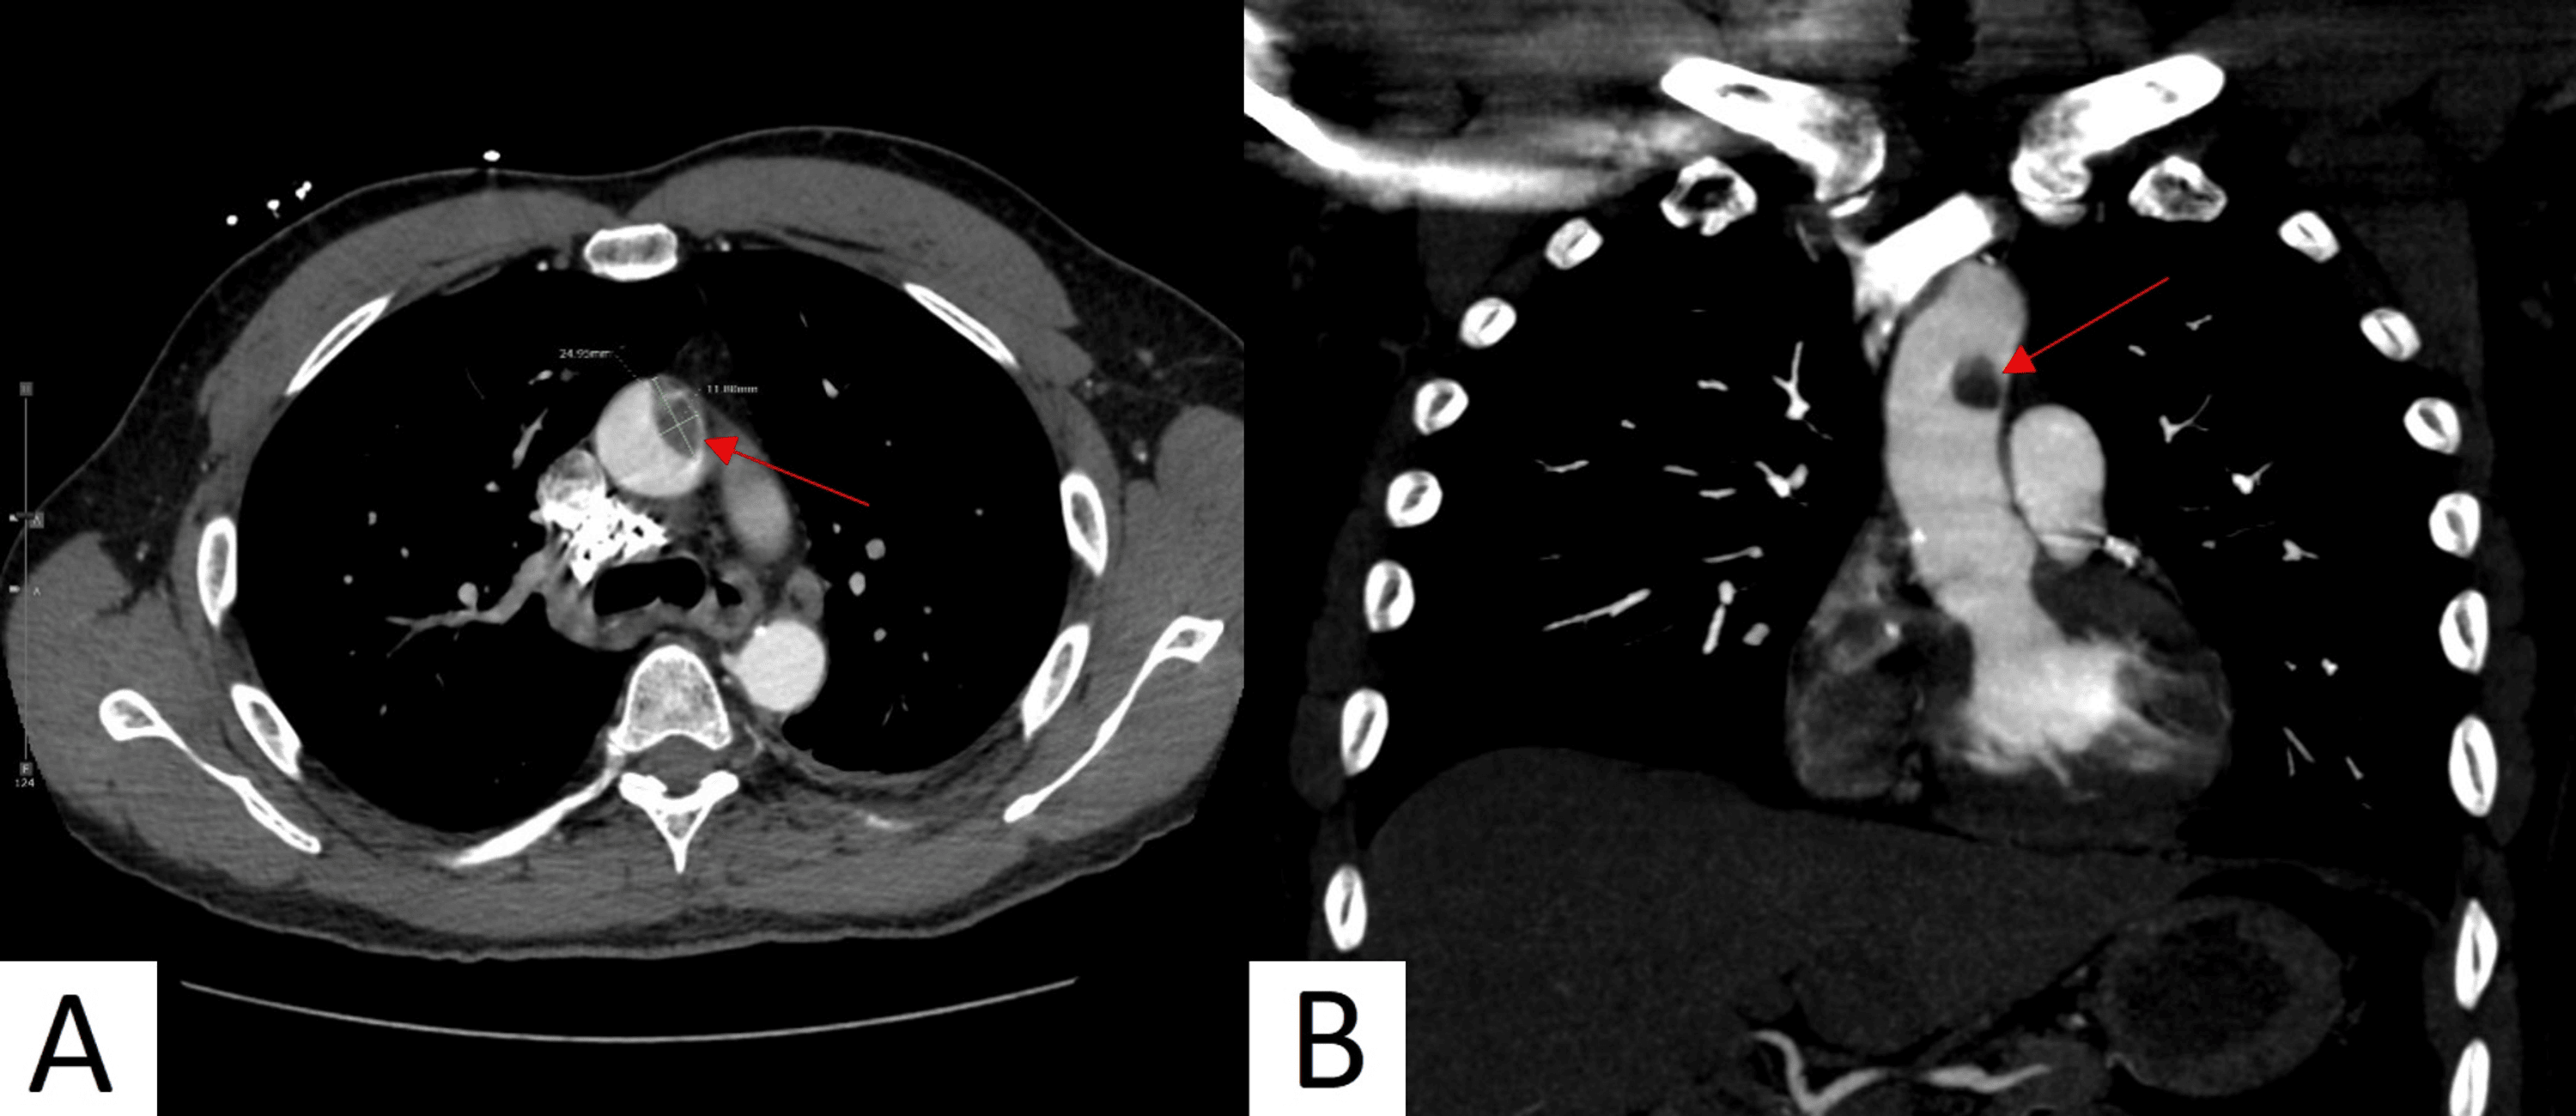

From www.cureus.com

CocaineInduced Ascending Aortic Thrombus Cureus What Is A Mural Thrombus Aorta Aortic mural thrombus in a nonaneurysmal minimally atherosclerotic or normal aorta is a rare clinical entity and an. Mural thrombus occurrence in a normal or minimally atherosclerotic. A mural aortic thrombus may form with aortic dissection, aortic aneurysm, malignancy, and blood disorders and is rarely seen in a healthy. Thoracic aortic mural thrombus (tamt) of the descending aorta is rare. What Is A Mural Thrombus Aorta.